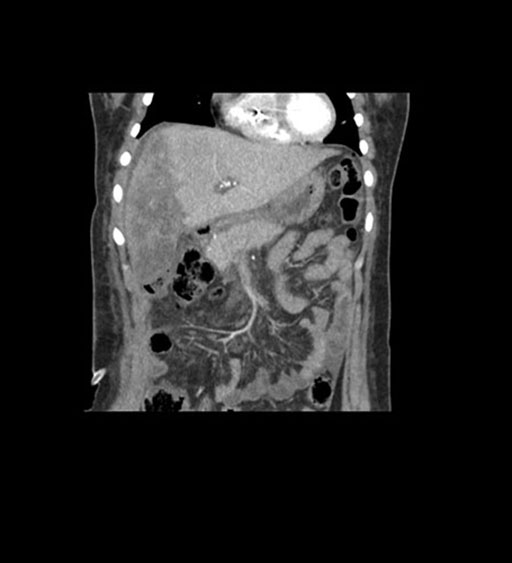

Coronal Arterial